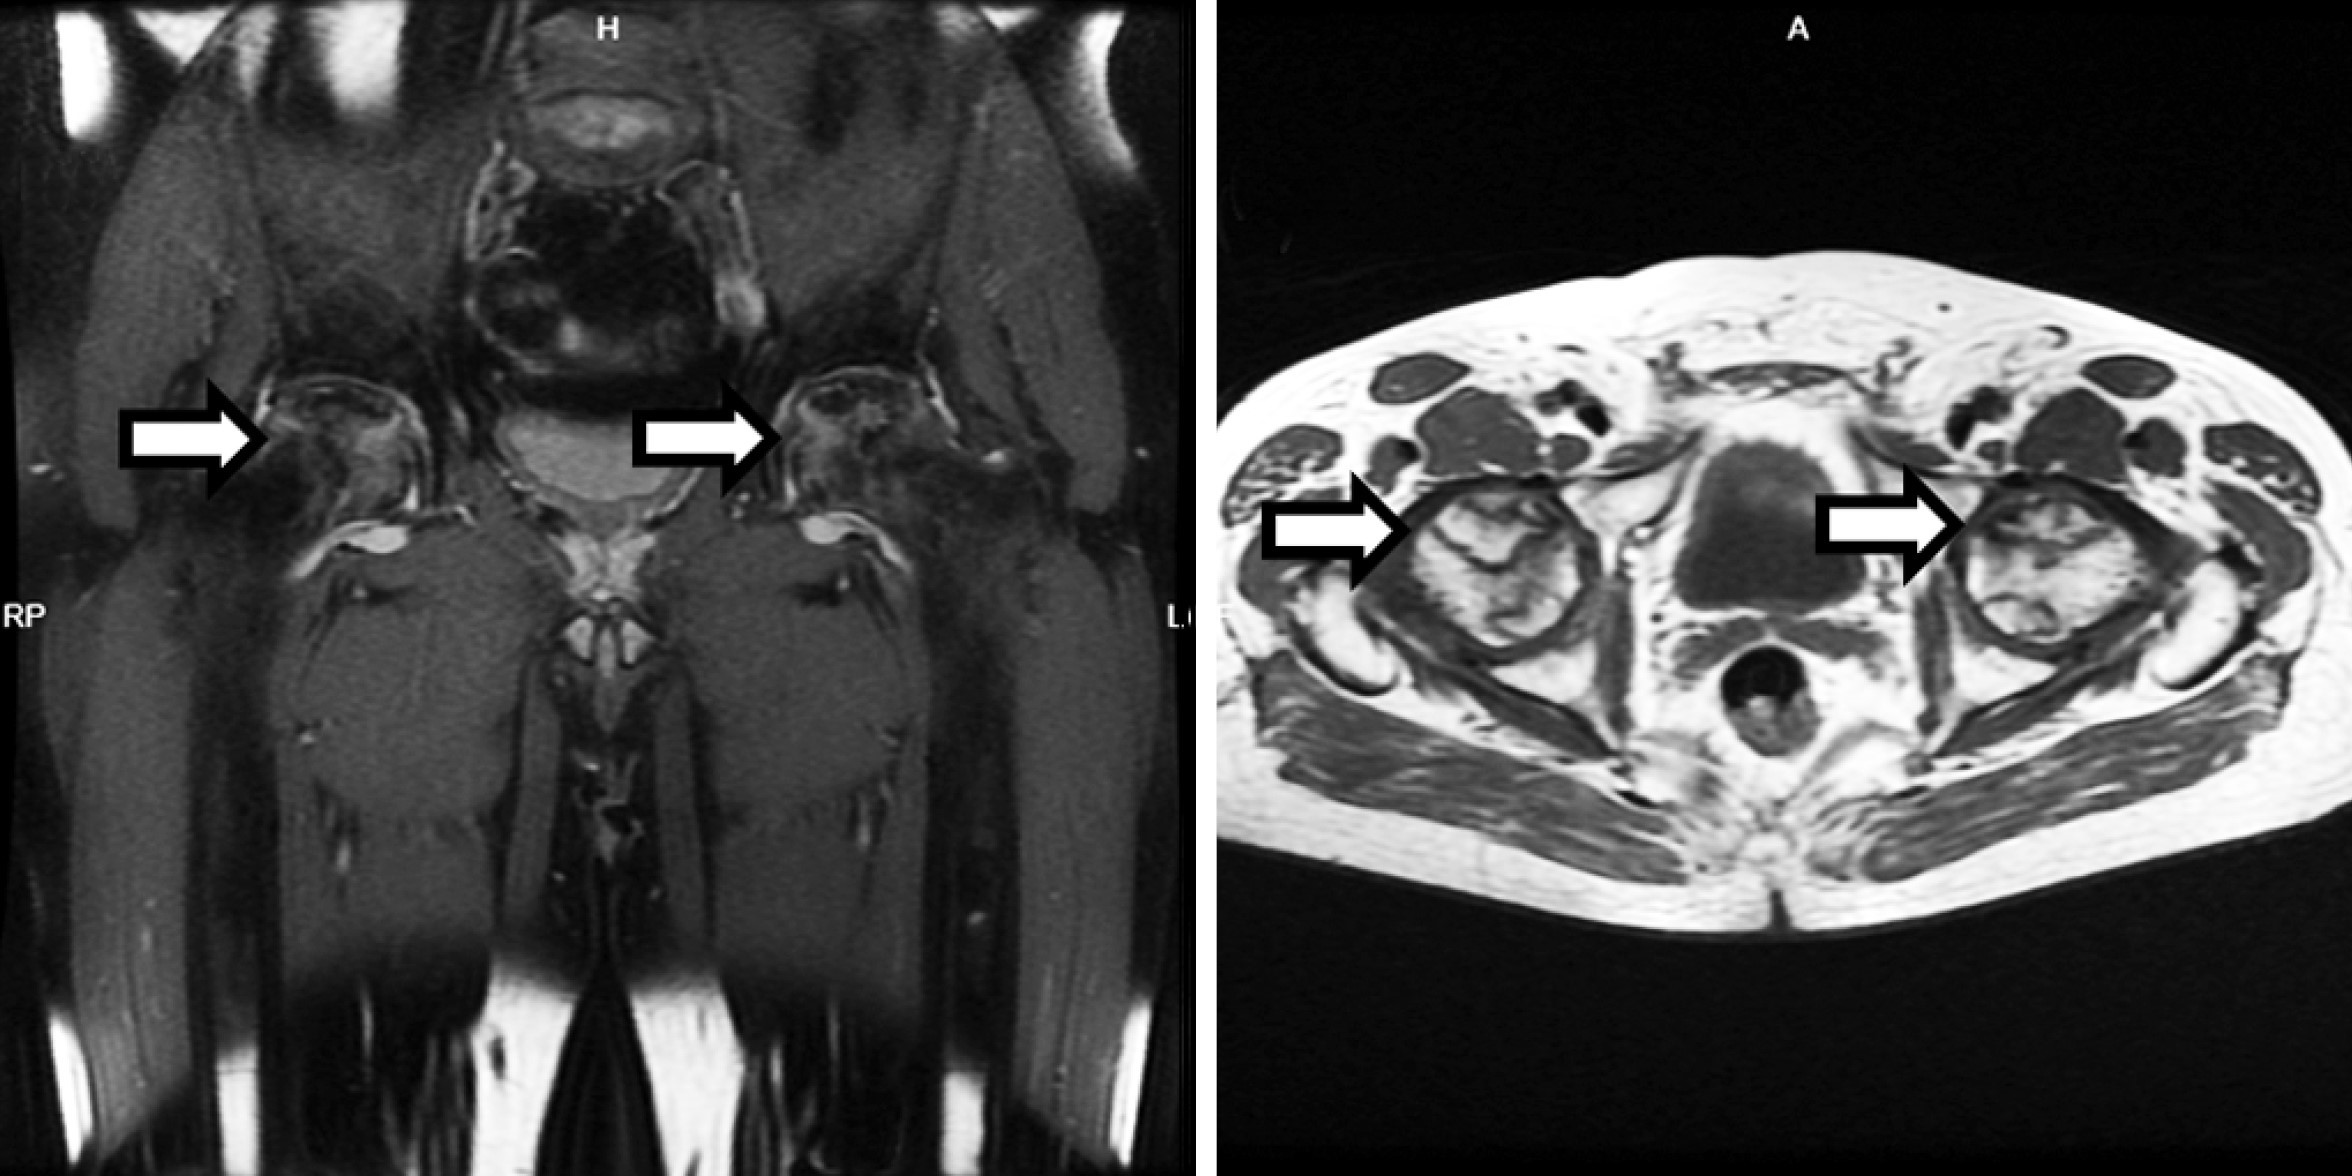

Five months after the onset of the symptoms, a hip MRI was performed due to the persistent nature of the hip pain. The MRI revealed multiple areas of AVN in both femoral heads, with lesions measuring up to 3.5 cm in diameter (Figure 1). The patient was diagnosed with stage III AVN of the femoral heads according to the ARCO classification [8], indicating a late-stage presentation with femoral head collapse. In addition to hyperbaric oxygen therapy aimed at preserving joint function and delaying the need for surgical intervention, the patient was prescribed NSAIDs and physiotherapy. The physiotherapy included range-of-motion exercises to maintain joint mobility and reduce stiffness. Despite these interventions, the patient’s pain persisted, necessitating further treatment options.

Figure 1. MRI revealing multiple areas of femoral head avascular necrosis (marked with white arrows)